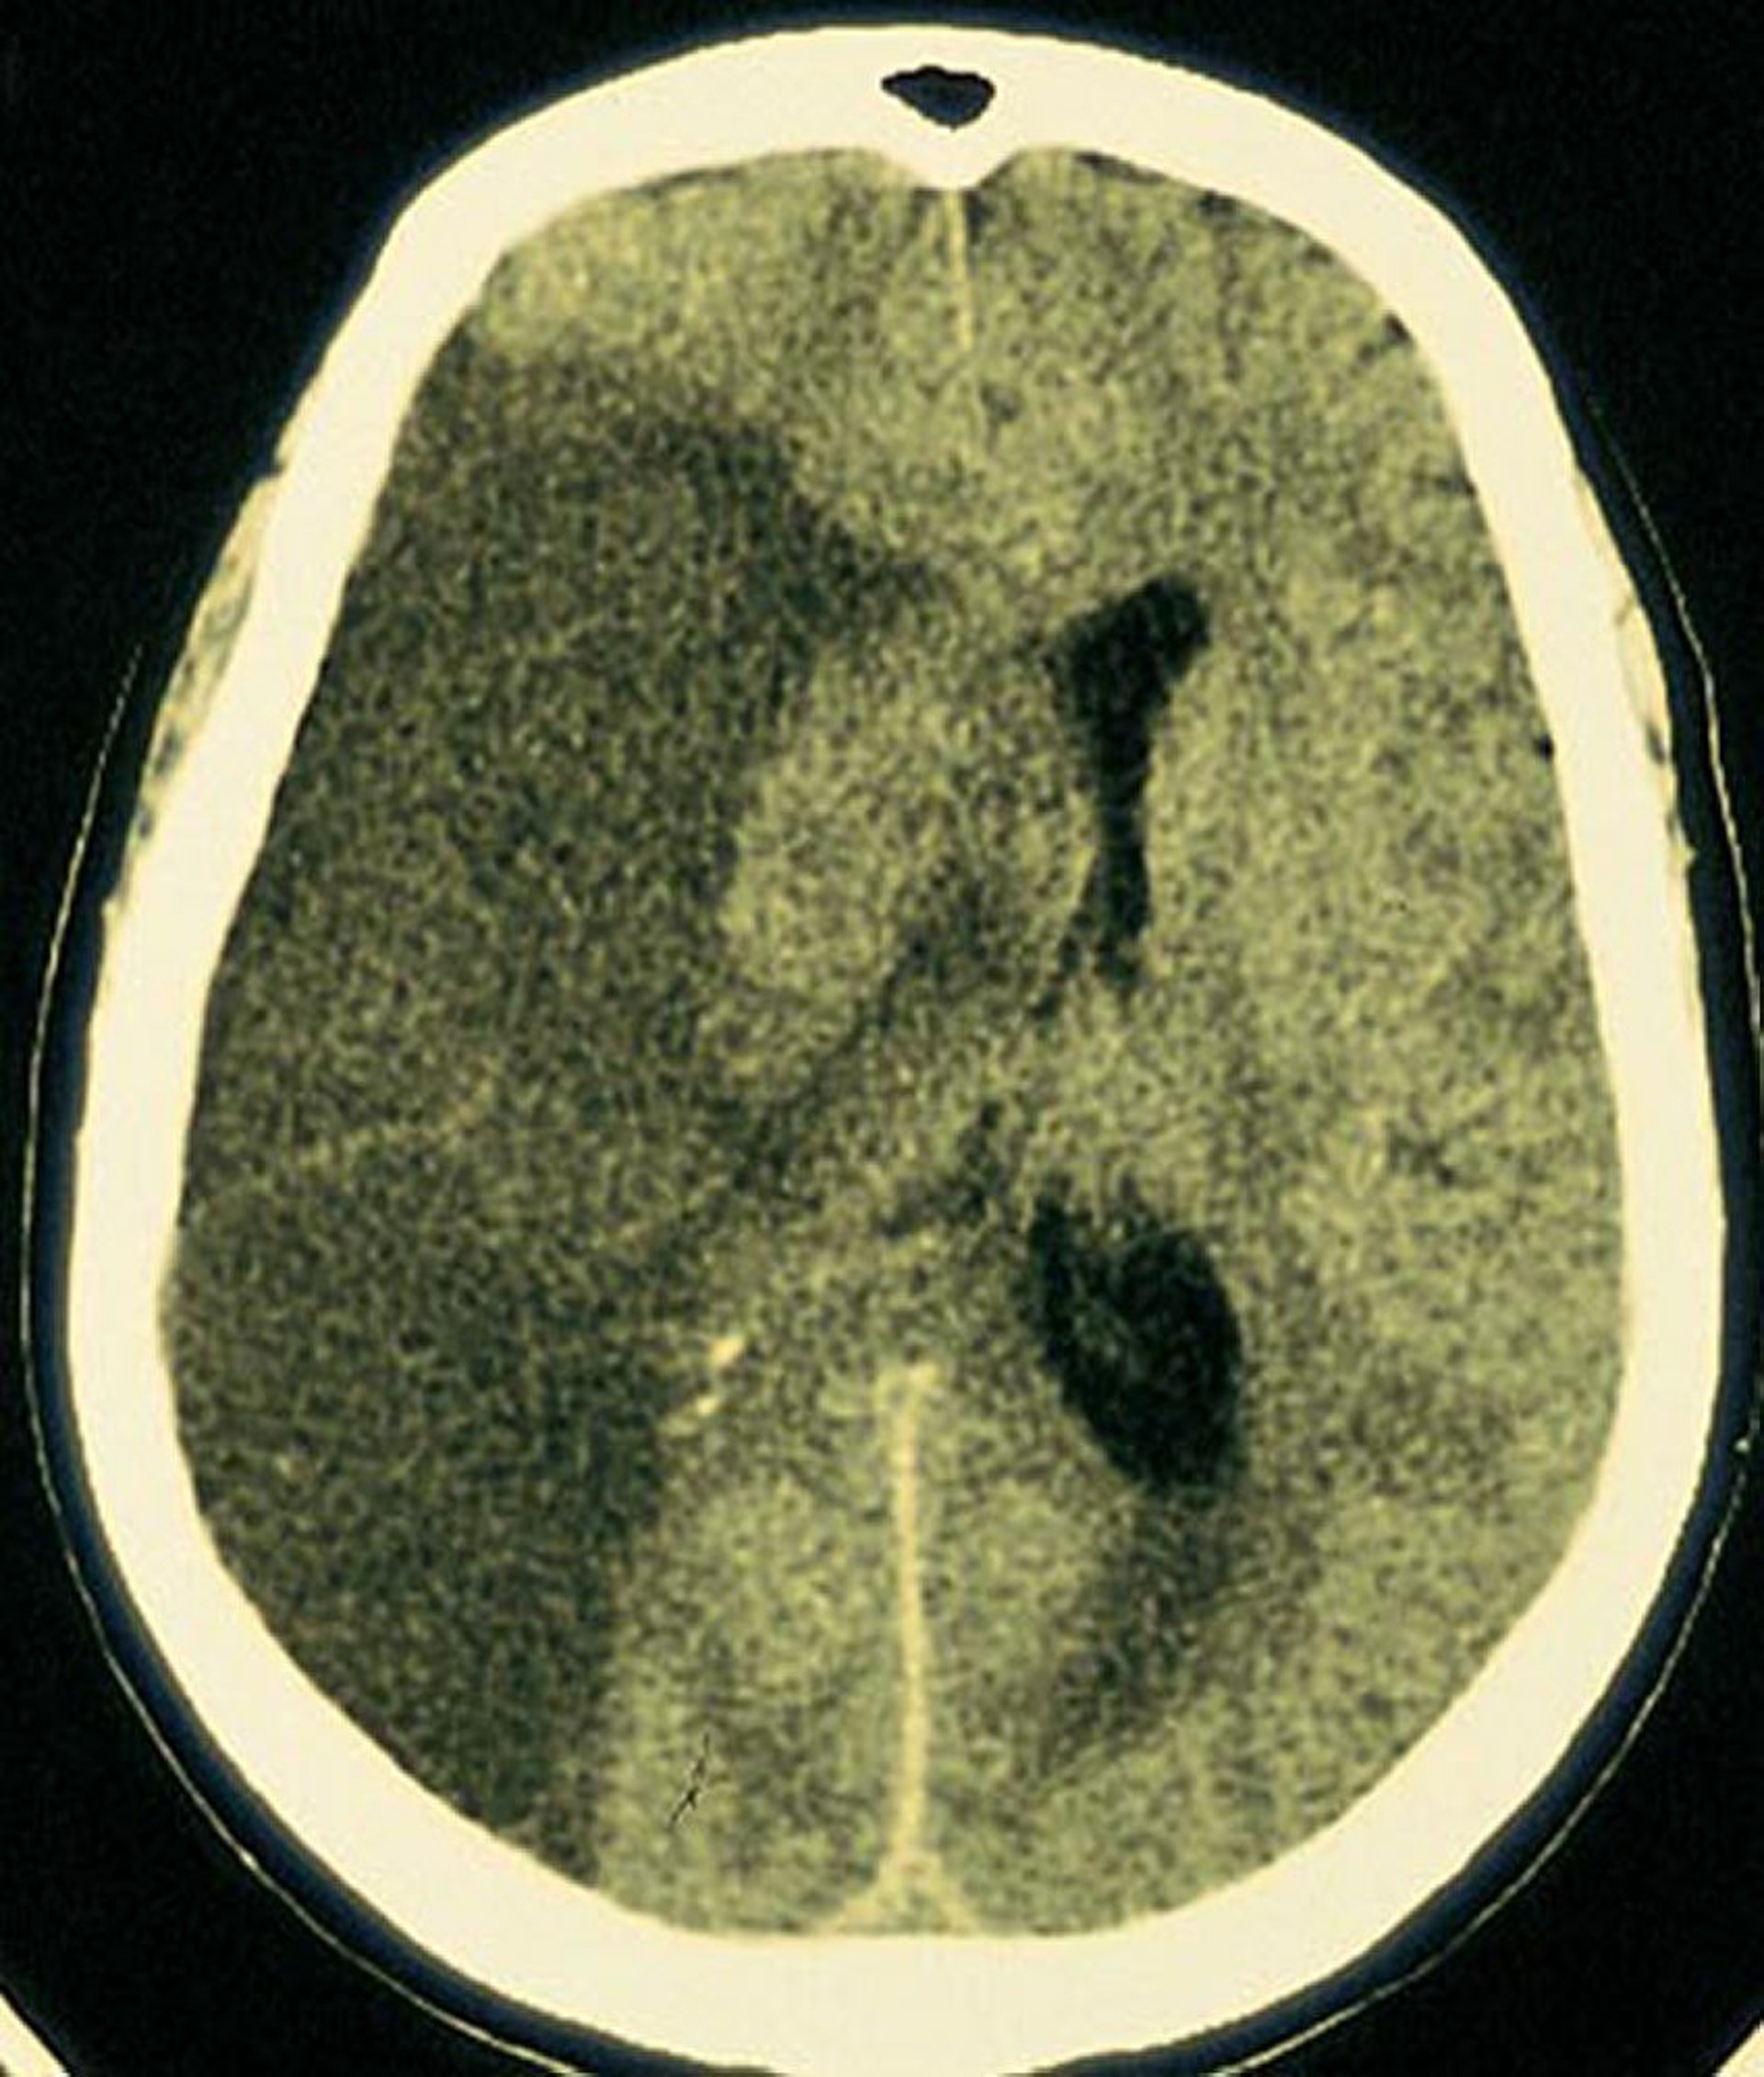

Инфаркт средней мозговой артерии

В области головного мозга, снабжаемого правой средней мозговой артерией, виден большой светлый очаг инфаркта.